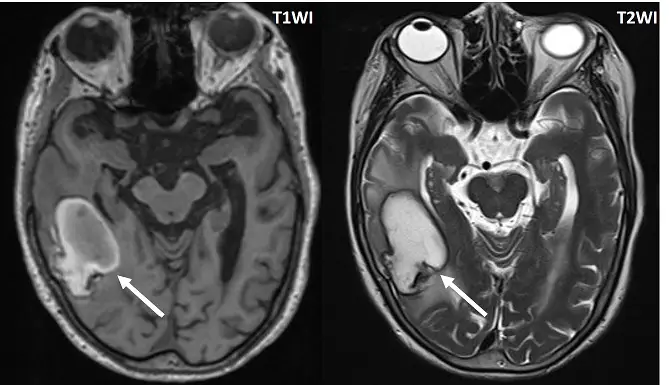

T1WI 及T2WI箭號所示之病灶如下圖,最有可能的診斷為何?

- T1WI(左圖):影像中右側顳頂葉(temporal-parietal region)可見一巨大病灶。該病灶的周邊呈現厚實的明顯高訊號(hyperintense),其亮度與頭皮下方的皮下脂肪相近;病灶中心則呈現等訊號(isointense)至稍低訊號。此厚實的周邊高訊號為典型的正鐵血紅素(methemoglobin)表現。

- T2WI(右圖):同一病灶在 T2WI 上,中心呈現高訊號(hyperintense),而病灶最外圍具有一圈極為明顯的低訊號黑環(hypointense rim)。此外,在低訊號環的外側,可見不規則的 T2 高訊號帶,代表伴隨的血管性水腫(vasogenic edema)。T2WI 的低訊號周邊黑環代表巨噬細胞吞噬紅血球後所形成的血鐵質(hemosiderin)沉積。

- 綜合分析:血腫的降解演進通常由周邊向中心發展。此影像顯示周邊已形成正鐵血紅素(T1高訊號)與血鐵質(T2黑圈),而中